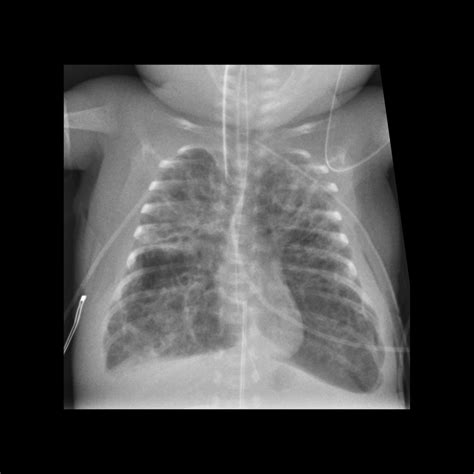

ARDS is a complex syndrome that can be triggered by various factors, including sepsis, pneumonia, trauma, and aspiration. It is marked by the rapid onset of bilateral pulmonary infiltrates, refractory hypoxemia, and decreased lung compliance. The Ards Chest X Ray is instrumental in visualizing these pulmonary infiltrates, which appear as diffuse, bilateral opacities on the radiograph.

The Ards Chest X Ray is often the first imaging modality used to evaluate patients suspected of having ARDS. It provides a quick and relatively inexpensive way to assess the lungs for signs of inflammation and edema. Key findings on an Ards Chest X Ray include:

• Bilateral pulmonary infiltrates

• Diffuse opacities

• Air bronchograms (air-filled bronchi surrounded by consolidated lung tissue)

• Absence of pleural effusions or cardiomegaly

These findings, when combined with clinical criteria such as the PaO2/FiO2 ratio (the ratio of arterial oxygen partial pressure to fractional inspired oxygen), help confirm the diagnosis of ARDS.

• Bilateral Infiltrates: ARDS typically presents with bilateral, diffuse infiltrates that are often more pronounced in the dependent lung zones.

• Air Bronchograms: These are visible air-filled bronchi within consolidated lung tissue and are a hallmark of ARDS.

• Absence of Pleural Effusions: Unlike other causes of pulmonary edema, ARDS is usually not associated with significant pleural effusions.

• Cardiomegaly: The heart size is typically normal in ARDS, helping to differentiate it from cardiogenic pulmonary edema.